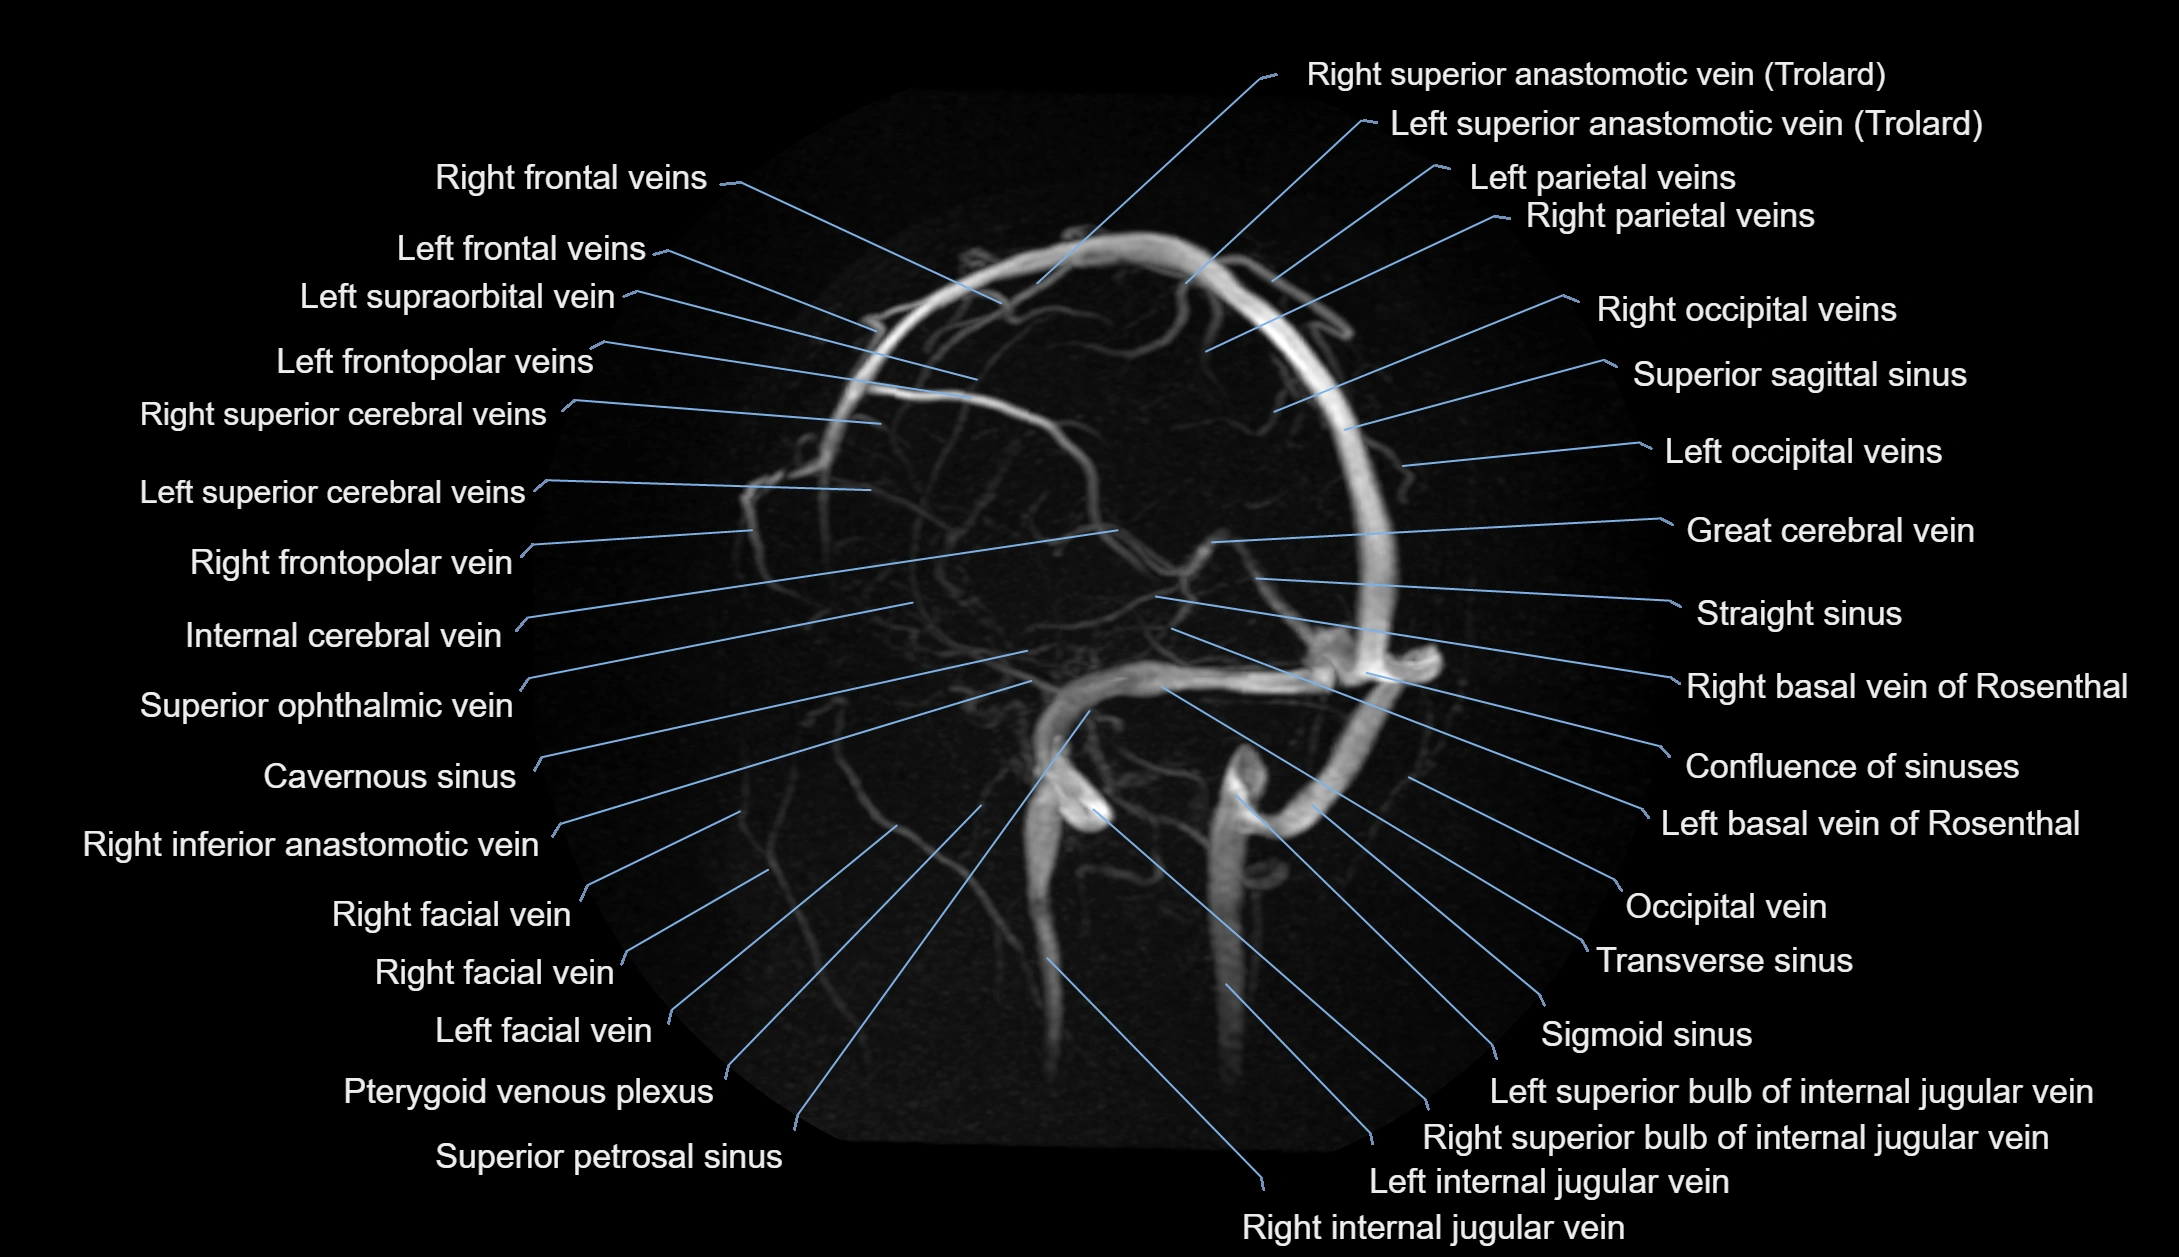

MR Venography (MRV):

• Time-of-flight (TOF) or contrast-enhanced MRV shows the angular vein as a bright enhancing venous channel

• Clearly demonstrates its continuity with the facial vein and superior ophthalmic vein

• MRV is highly useful in evaluating thrombosis, venous obstruction, or collateral venous drainage